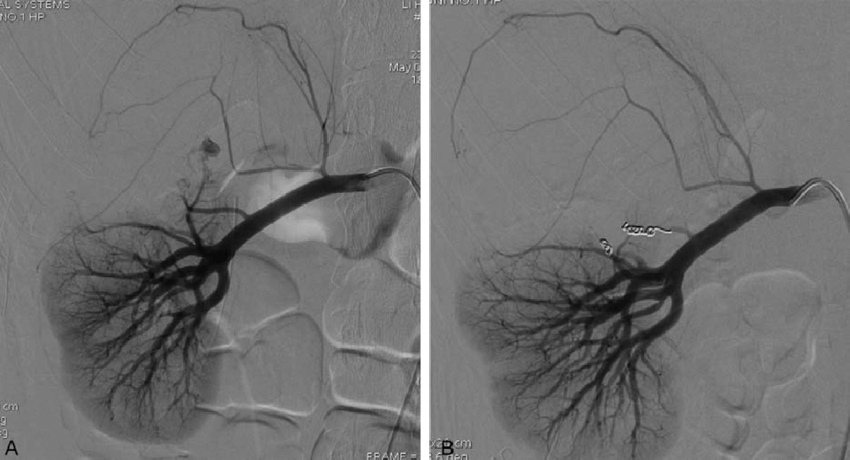

Renal angiography of RAP before and after TAE. (A) Angiography showed a pseudoaneurysm after LPN. (B) Angiography after coil embolization revealed the disappearance of the RAP. LPN = laparoscopic partial nephrectomy, RAP = renal arterial pseudoaneurysm, TAE = transarterial embolization.